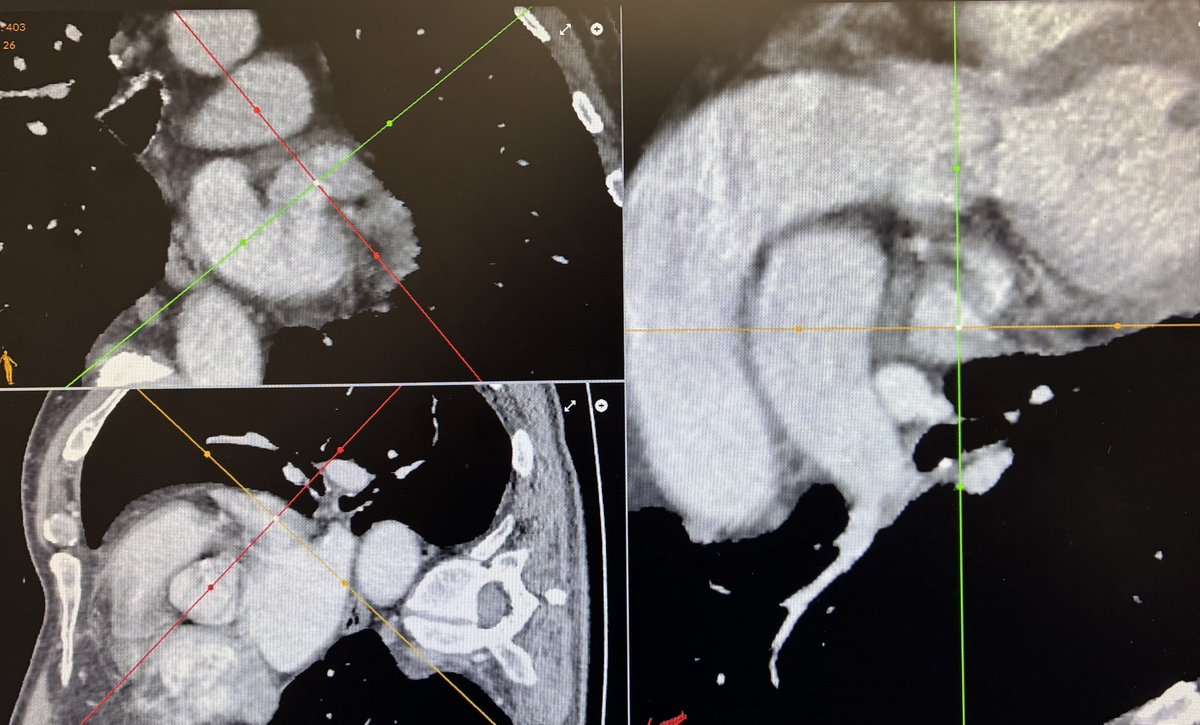

Discusión sobre distintas técnicas de imagen y herramientas de planificación en las que nos apoyamos

Tres casos, tres, de cierre de orejuela en vivo con Amulet (uno de ellos con electroporación de venas pulmonares) que han ido genial gracias a la colaboración y coordinación de grandes profesionales